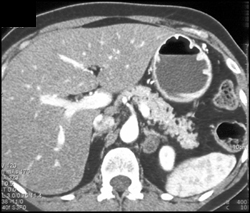

Gastric Cancer